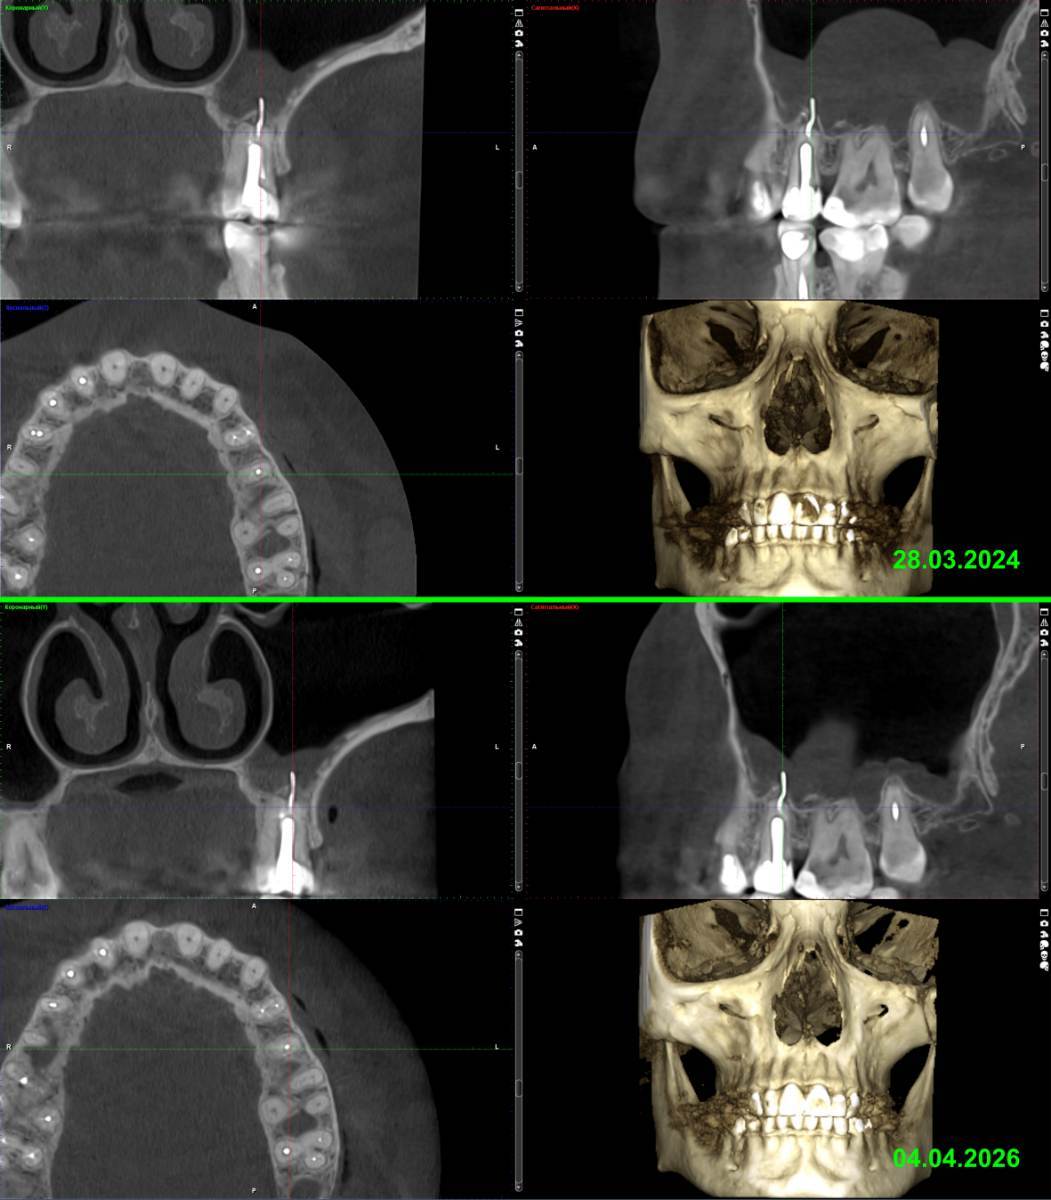

safroxa Опубликовано 14 апреля Поделиться Опубликовано 14 апреля (изменено) Здравствуйте дорогие доктора, очень хотелось бы послушать ваши мнения, ситуация такова: в 2023 году пролечила зуб №25, его можно сказать собрали из ничего, поставили огромный штифт и сразу же порекомендовали накрывать коронкой... По совету другого доктора решили понаблюдать за зубом и коронками не накрывать. В итоге на КТ наблюдается выход материала в пазуху, киста (воспаление), хирург рекомендует удалять этот зуб. Может быть есть смысл сделать резекцию или шансов для этого зуба 0? Подскажите пожалуйста решение, заранее благодарю. Ссылка на более качественное изображение снимков https://disk.yandex.ru/i/u07qjP042Lrfhw Изменено 14 апреля пользователем safroxa Ссылка на комментарий

safroxa Опубликовано 15 апреля Автор Поделиться Опубликовано 15 апреля @Doc спасибо за ответ, если сравнить прошлое кт, в воспаление в пазухе уменьшилось - тогда может пока не трогать этот зуб, а пусть стоит пока стоит? Ссылка на комментарий

safroxa Опубликовано 15 апреля Автор Поделиться Опубликовано 15 апреля @Doc доктор, а в пазухе воспаление из-за выведенного материала? Нет там какой-то кисты? И если нет и я надумаю удалить этот зуб, то главное чтобы этот выведенный материал вышел вместе с зубом и тогда в теории воспаление должно совсем уйти? @red_butler Здравствуйте доктор, а какое тогда решение? Ссылка на комментарий

safroxa Опубликовано 15 апреля Автор Поделиться Опубликовано 15 апреля @red_butler доктор, перелечивание должно проводиться под микроскопом? И если потребуется резекция апекса, то должна быть сделана ретроградная пломбировка? И доктор, вы не видите в пазухе "кисту"? В теории в пазухе воспаление из-за выведенного гуттаперчевого штифта? Или сделанные мной снимки экрана неинформативны? Ссылка на комментарий